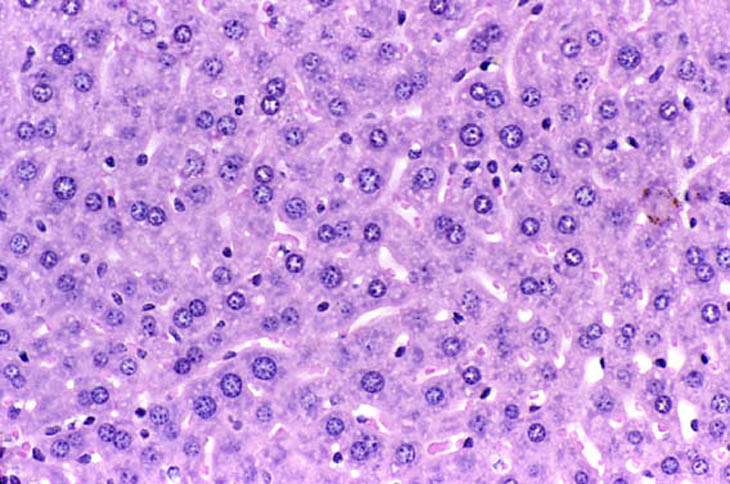

Immersion fixed liver following an overnight fast. Fixative was 10% NBF.